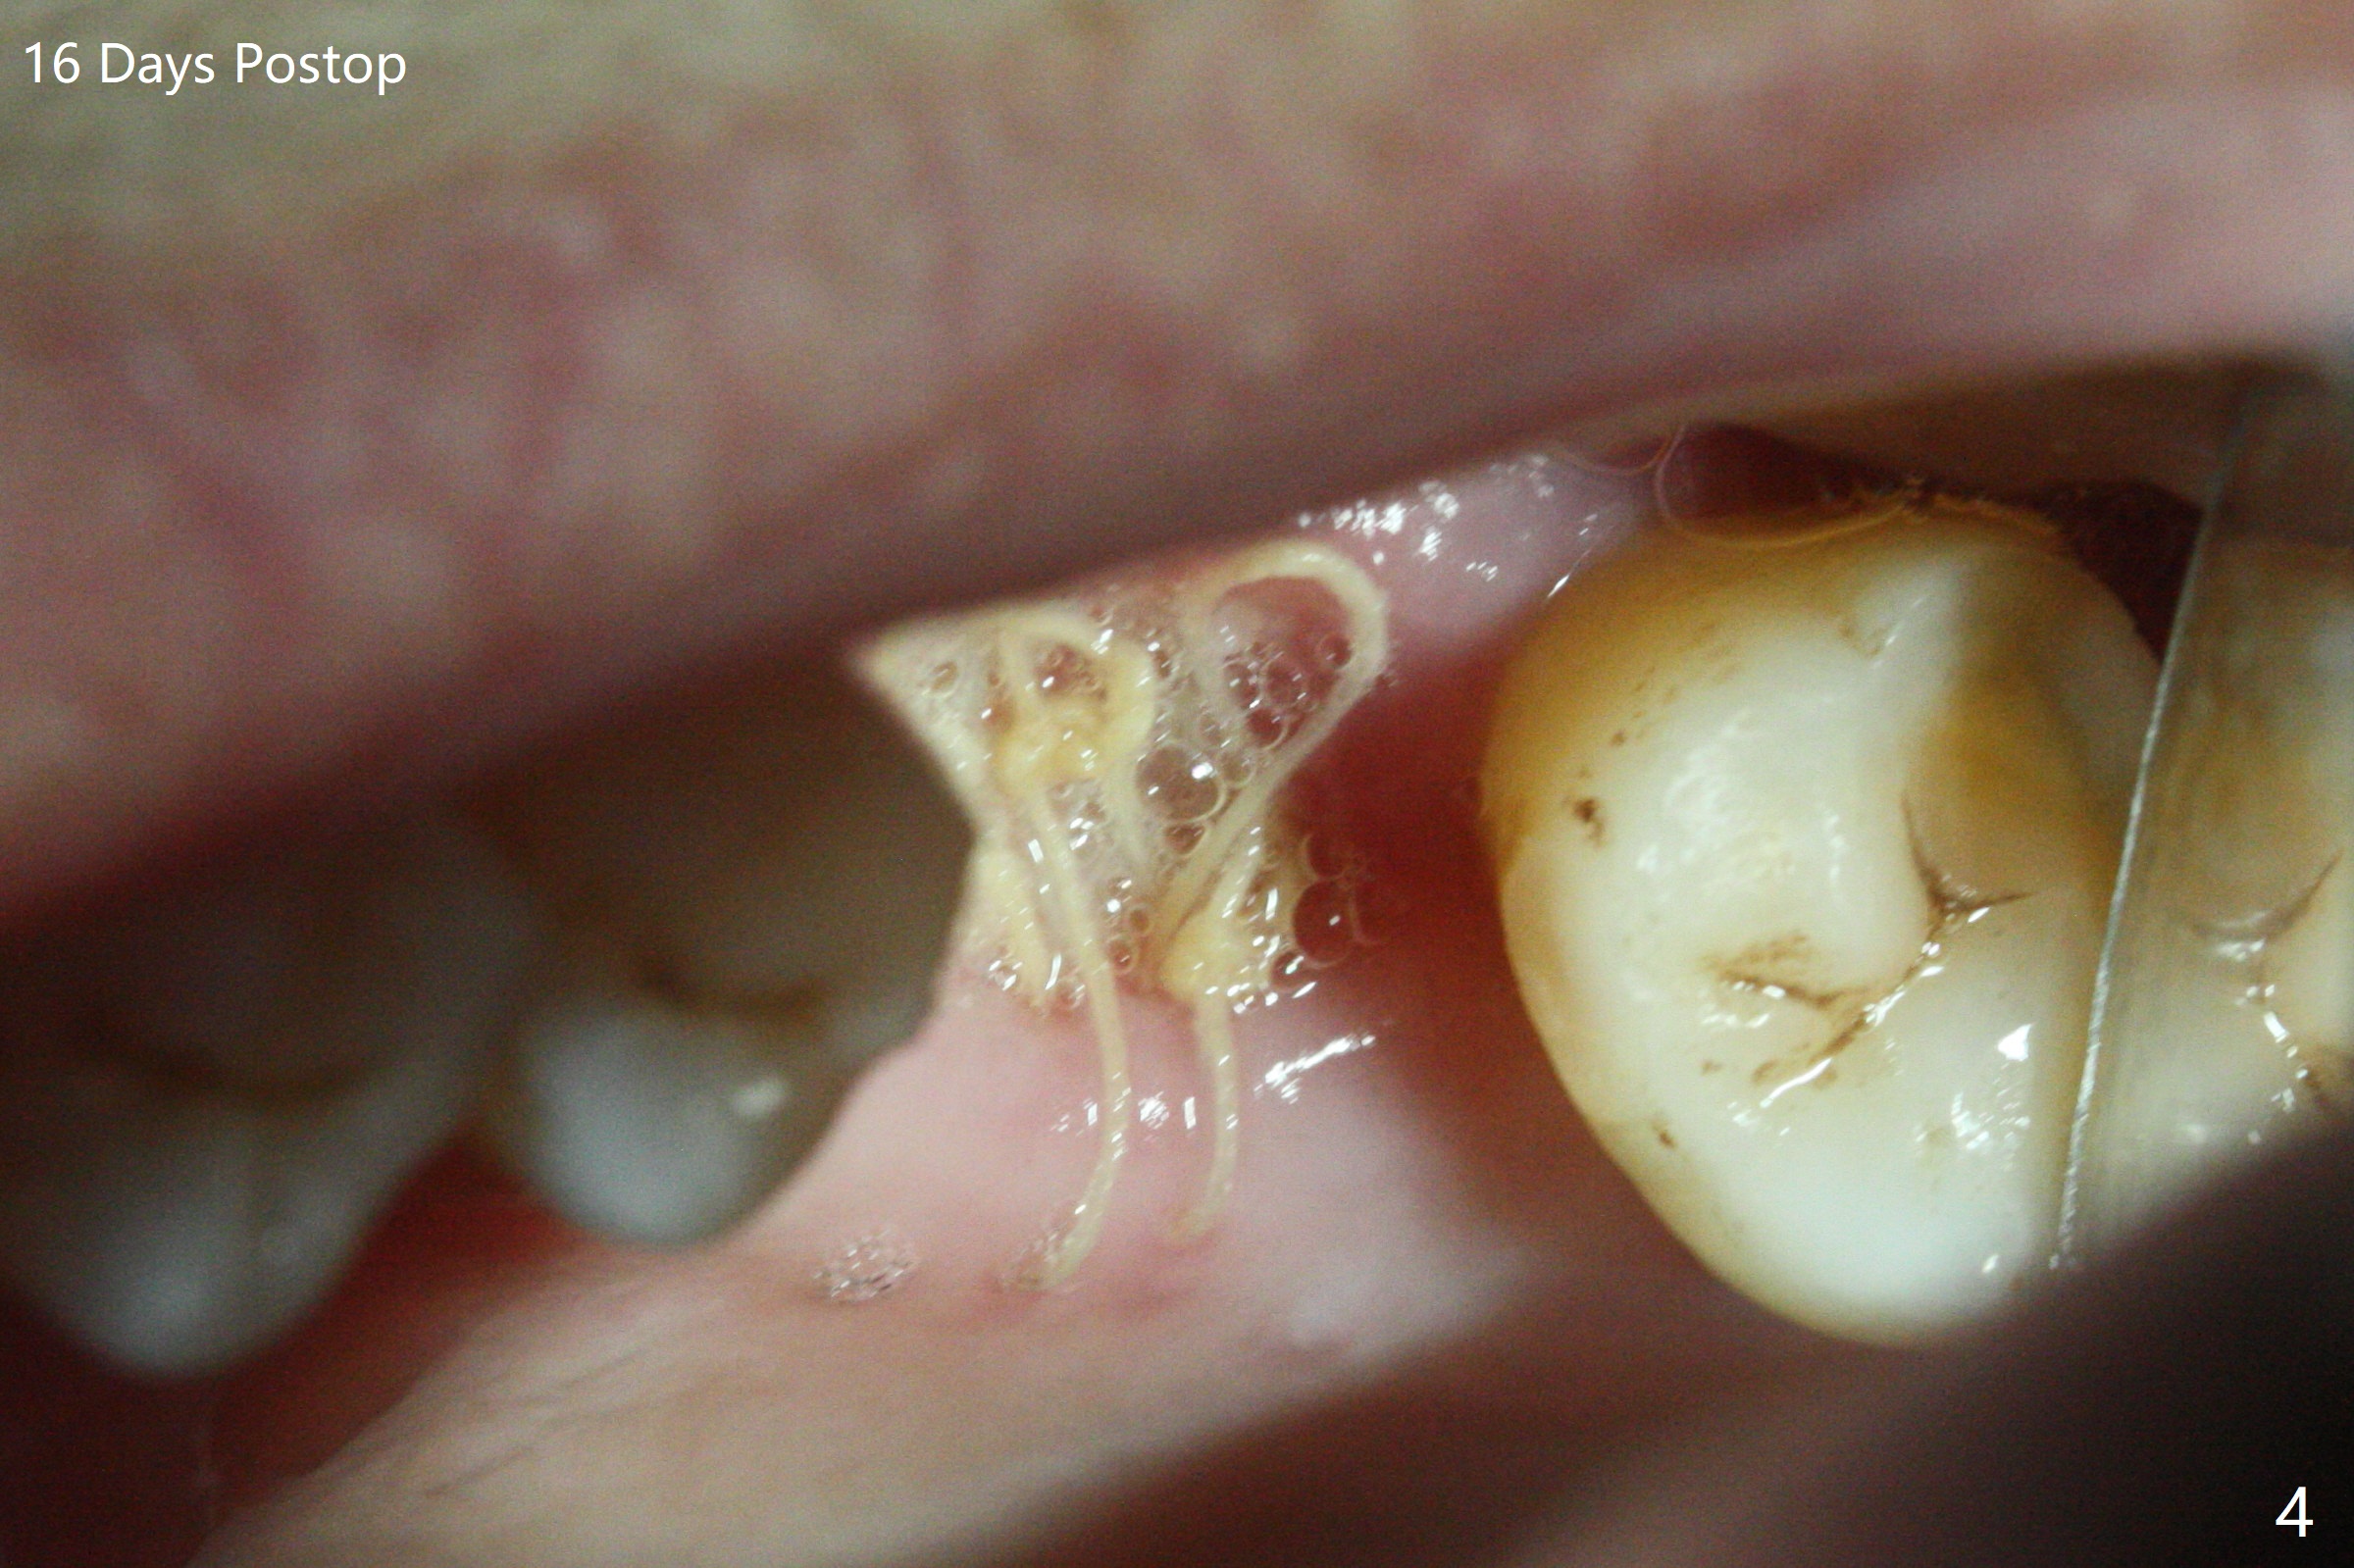

67岁女深洗后突然回来要求拔除左上六(图一),颊侧红肿,流脓,牙周袋深(图二B),经过多番劝导,终于图一植骨,由于时间仓促,使用合成血小板生长因子(GEM21S,而不是PRF))与皮质骨(125μm – 850μm)以及皮松质骨(500μm – 1,000μm)调拌,放置于巨大吸收融合颊侧牙槽窝(图三*(无颊侧骨板)(使用condenser)),而腭侧牙槽窝没有明显破坏(图一P),放置Osteogen Plug(一种骨胶原, 图三 O)。牙槽窝口放置胎盘膜(BioXclude),使用4/0 PGA缝线。傍晚病人已经 没有肿痛了。术后十三天牙周敷料脱落,伤口愈合良好。三天后病人又回来复诊(图四),折线后,虽然伤口愈合,骨粉好像填的不够多(图五),或者丢失。树脂敷料可能取得更好的结果。